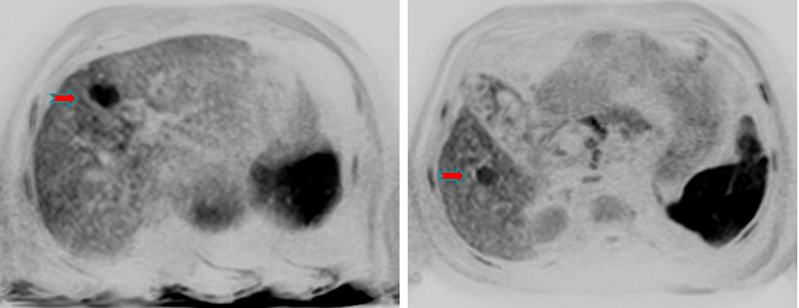

应用瑞戈非尼1个月,MRI示,DWI信号明显增浓,肿块缩小;应用瑞戈非尼2个月,MRI示,DWI信号变淡,基本消失,肿块缩小(图3)。

图3.应用瑞戈非尼联合PD-1抑制剂治疗1个月和2个月复查MRI

2021年5月复查MRI,发现一个新发病灶,DWI信号增浓(图4)。AFP上升至119.17ng/ml。

图4.2021年5月复查MRI

2021年6月复查MRI示,DWI信号明显变淡(图5)。

图5.2021年6月复查MRI